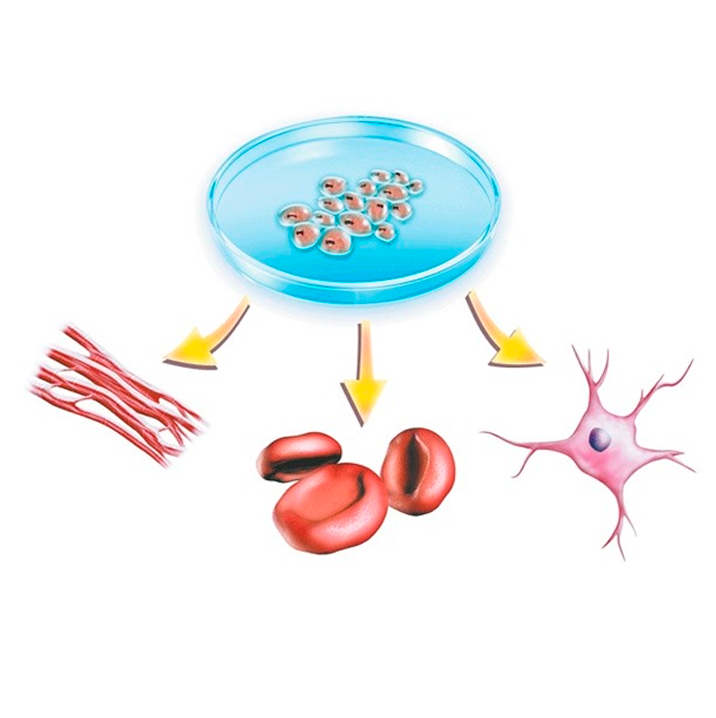

- Ver expedienteCriopreservacion de celulas madre